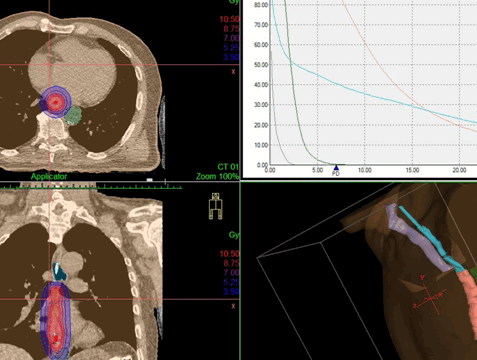

Дозное распределение, получаемое при дистанционной конформной лучевой терапии и внутрипросветной брахитерапии

- Контактное (называется «брахитерапия»). Источник излучения эндоскопическим методом размещается как можно ближе к новообразованию. Ионизирующие лучи проходят малое расстояние, поэтому достигают опухоли, но мало затрагивают расположенные рядом ткани. Лечение позволяет уменьшить новообразование и восстановить проходимость.

- Наружное (дистанционное). Источник ионизирующего излучения находится на расстоянии от пациента.

Лучевая терапия

Применяется ионизирующее излучение с целью уничтожения клеток новообразования. Такая терапия может проводиться: